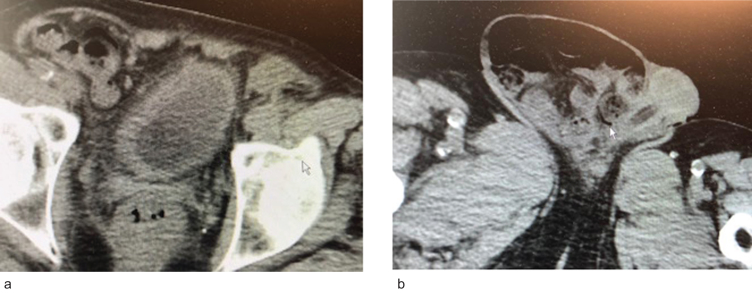

RS是一名81岁的男性,2010年有低、高级别膀胱癌病史。直到2020年,他都没有膀胱癌。到2016年,他进行了常规的办公室膀胱镜检查和细胞学检查,2016年至2020年仅进行了尿液检查。他有慢性心房颤动和冠状动脉疾病。他已经植入了两个心脏支架。他吃香豆素。2014年,他曾因肉眼血尿短暂入院,但出血消退了。他的肌酐是2.80。非对比CT扫描显示两个小肾脏,符合内科肾病。扫描还显示前列腺肿大和长期存在的右侧腹股沟大阴囊疝(图1)。疝已存在多年,症状轻微。病人不想要修复。当时他的肌酐是2.80。2020年10月,患者再次出现肉眼血尿。慢性肾功能衰竭有明显的优势